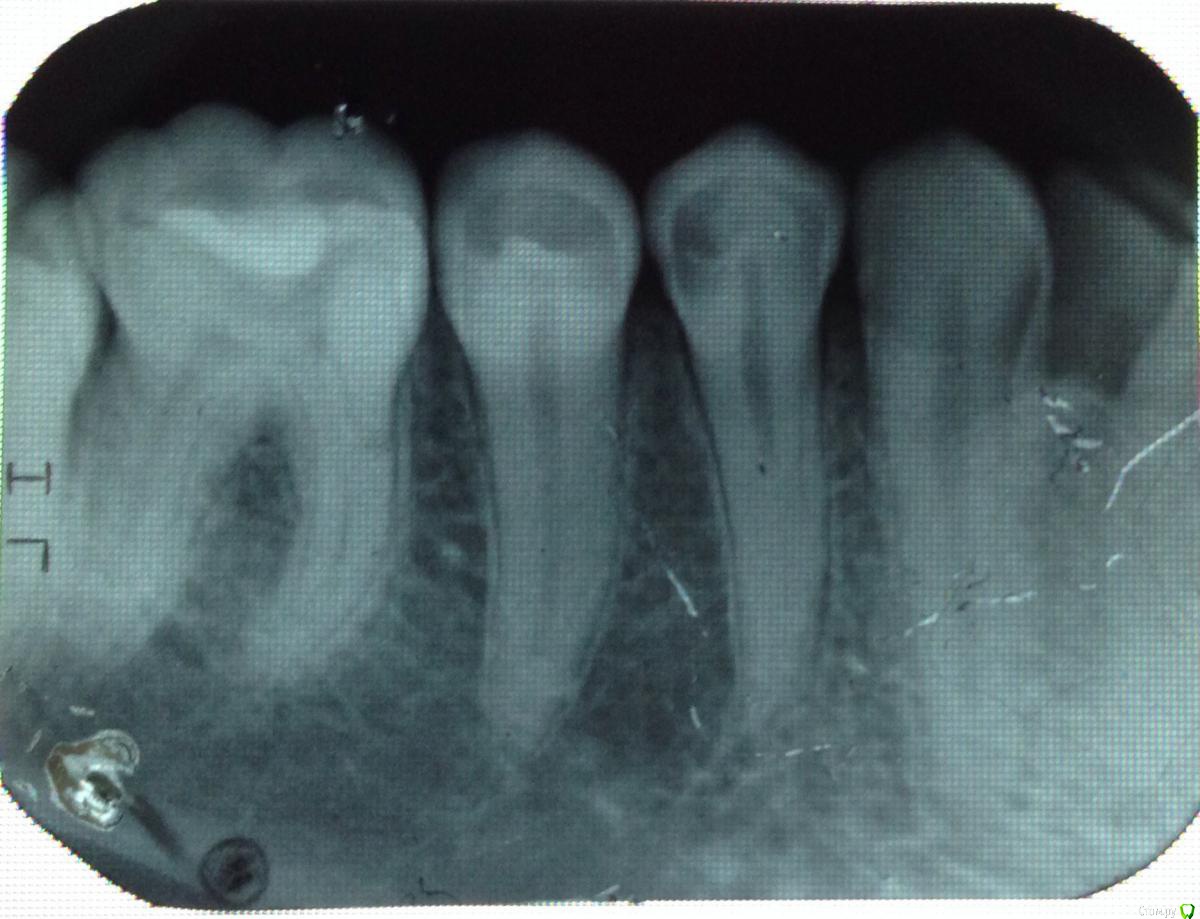

Даночка Опубликовано 6 мая, 2015 Поделиться Опубликовано 6 мая, 2015 Здравствуйте!В 34 зубе есть кариес(снимок 1)? Если да, то какой интенсивности? Есть ли кариес в 27(снимок 2)? Если да, то какой? Врач по внешнему осмотру сказал, что фиссурный. Так ли это? Ссылка на комментарий

Гарриевич Опубликовано 6 мая, 2015 Поделиться Опубликовано 6 мая, 2015 Фиссурный кариес на регнгенограмме не виденНа 34 есть, со стороны 35 достаточно глубокий 1 Ссылка на комментарий